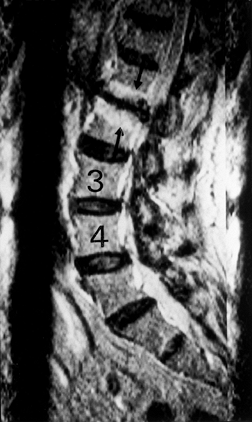

(MRI) is the most commonly employed imaging modality. In that MRI can

directly measure water content of the disc, it is the only imaging

technique that can detect biochemical changes in the nucleus (56,61).

The normal, hydrated NP has an increased proton signal on T2 images.

With increasing desiccation, this signal blends with that of the

surrounding annulus. With further degeneration, a dark, isointense

signal may be seen on T2 (Fig. 145.10, Fig. 145.11).

![]() |

|

Figure 145.10. Sagittal T1-weighted MRI depicting disc degeneration at L1–L2 with endplate sclerosis (asterisk).

Figure 145.11. Sagittal T2-weighted MRI depicting black disc at L1–L2 with typical endplate changes (arrow).